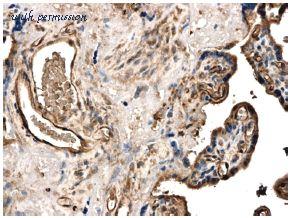

gene information - human MMP25

- synonym:MMP-25; MMP20; MMP20A; MMPL1; MT-MMP 6; MT-MMP6; MT6-MMP; MT6MMP; MTMMP6

- description:matrix metallopeptidase 25